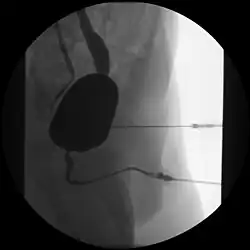

Im Gegensatz zur Urethroskopie im Rahmen einer Zystoskopie als optisches Verfahren mit Hilfe eines Endoskopes erfolgt die Urethrographie als Röntgen-Untersuchung mit Durchleuchtung und Gabe von Kontrastmitteln.

Die Untersuchung kann in Richtung des Urinflusses (antegrad) im Rahmen eines Miktionszystourethrogrammes erfolgen oder rückwärts (retrograd) als Retrograde Urethrographie (RUG) mit Darstellung der Harnblase.[1]

Bei männlichen Patienten erfolgt eine etwa 45° Schräglagerung und Abspreizung des Oberschenkels, so dass die Urethra möglichst ohne knöcherne Überlagerung darstellbar wird. Über die äußere Harnröhrenmündung an der Penisspitze wird über einen Katheter ein Kontrastmittel injiziert.